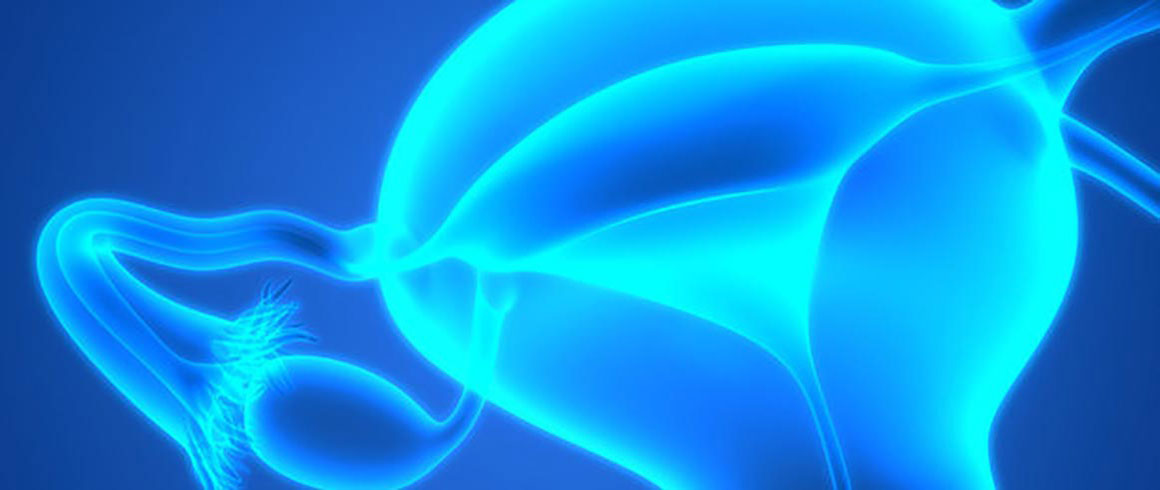

La sindrome dell’ovaio policistico (PCOS) è il più comune disordine endocrino-metabolico della popolazione femminile in età fertile, colpendo circa il 7-10% delle donne giovani. In Italia, in particolare, colpisce tra il 5 e il 15% delle donne in età riproduttiva.

Il quadro clinico di tale sindrome è caratterizzato da un’eterogenea combinazione di assenza o ridotta ovulazione, irregolarità del ciclo mestruale, iperandrogenismo clinico (con visibile irsutismo) e/o laboratoristico (eccesso di ormoni maschili riscontrabile con prelievo di sangue), acne e presenza di numerosi follicoli (più di 10) di diametro compreso tra 3 e 9 mm e disposti prevalentemente lungo la periferia dell’ovaio, visibili all’ecografia. Il 30-70% delle donne con PCOS presenta, inoltre, obesità androide e dislipidemia e in oltre il 70% dei casi insulinoresistenza e iperinsulinemia compensatoria. Nelle donne con PCOS si osservano non infrequentemente le caratteristiche della sindrome metabolica (SM) e un incrementato rischio di sviluppare diabete mellito Tipo 2 e, probabilmente, anche patologie cardiovascolari. Interessando direttamente l’ovulazione, essa è associata a un calo di fertilità.